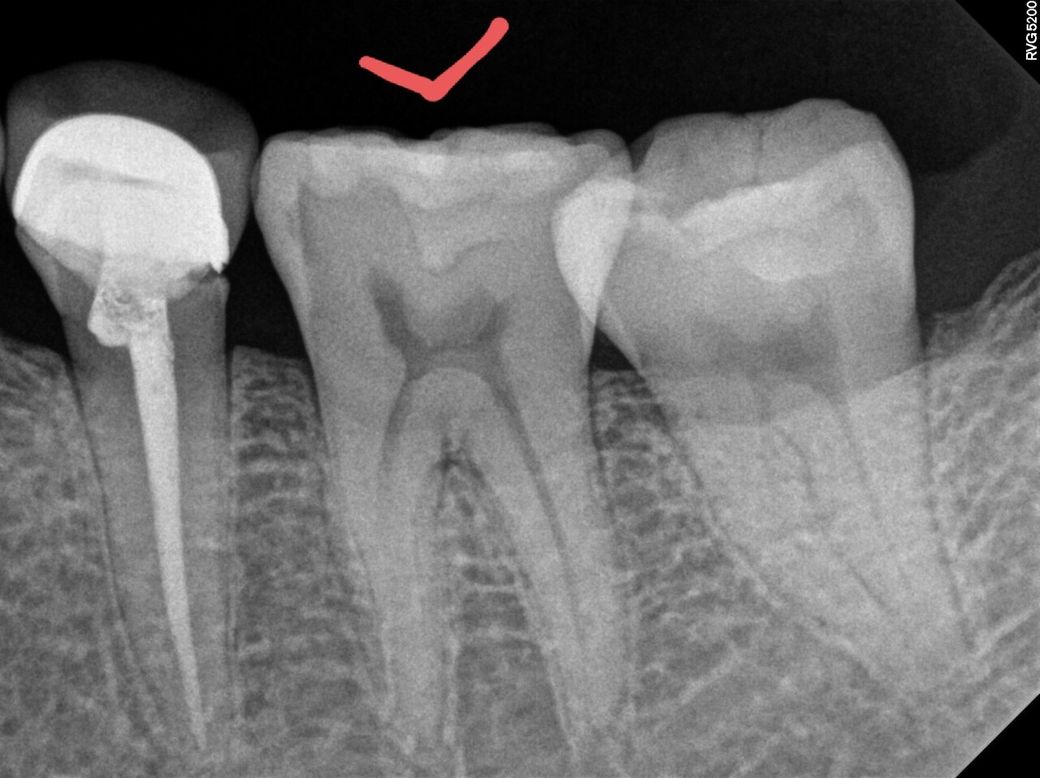

사진으로 봤을 경우에 보철물과 치아 사이에 음영이 보이는것로 봐서는 충치일수도 있지만 아닐수도 있습니다 .

육안으로 보철물과 치아 사이의 경계부위를 확인해 보거나 보철물을 제거해 보기 전에는 확신을 하기 힘들어 보여요.

사진상으로 보면 어금니 사이에 충치가 있는것같습니다. 일반적으로 사이에 충치가 있다면 인레이치료를 하게 됩니다. 증상이 있으셔서 제거해봐야 알겟지만, 인레이 치료는 신경치료 가능성이 있습니다. 치료를 받으시긴 받으셔야될것같습니다.